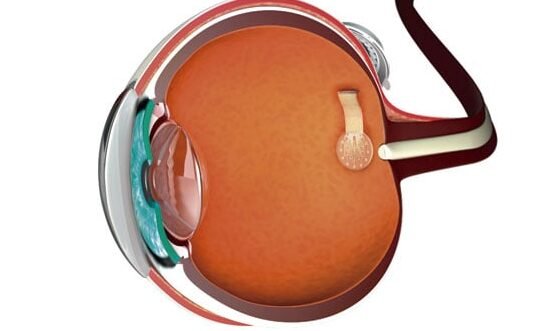

Los avances en la tecnología médica han permitido el desarrollo de innovadoras prótesis de retina para devolver...

Los lentes de contacto inteligentes para medir la presión intraocular representan un avance revolucionario en el campo...